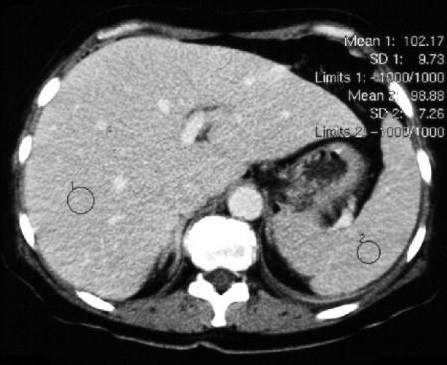

Image TDM de

steatose :

Normalement la densite du foie est

plus hyperdense de 6-12 UH que la rate . Par

infiltration de la graisse des cellules

hepatiques , la parenchyme devient fortement hypodense

( 30-40UH ) par rapport a une foie

normale ( normalement 50UH ) . Le foie est

steatosique quand sa densite en moindre 10 UH que la

rate . : |

Image TDM sans preparation :

Normalement la densite du foie 50UH et la rate est

40 - 45 UH . |

En coupe TDM avec contrast

intraveineuse : La densite du foie est 100UH et la

rate est de 75-100UH |